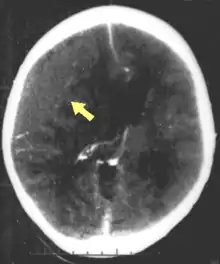

CT scan showing epidural hematoma (arrow)

Diagnosis is suspected based on lesion circumstances and clinical evidence, most prominently a neurological examination, for example checking whether the pupils constrict normally in response to light and assigning a Glasgow Coma Score.[32] Neuroimaging helps in determining the diagnosis and prognosis and in deciding what treatments to give.[76] DSM-5 can be utilized to diagnose TBI and its psychiatric sequelae.[77][78][79]

The preferred radiologic test in the emergency setting is computed tomography (CT): it is quick, accurate, and widely available.[80] Follow-up CT scans may be performed later to determine whether the injury has progressed.[27]